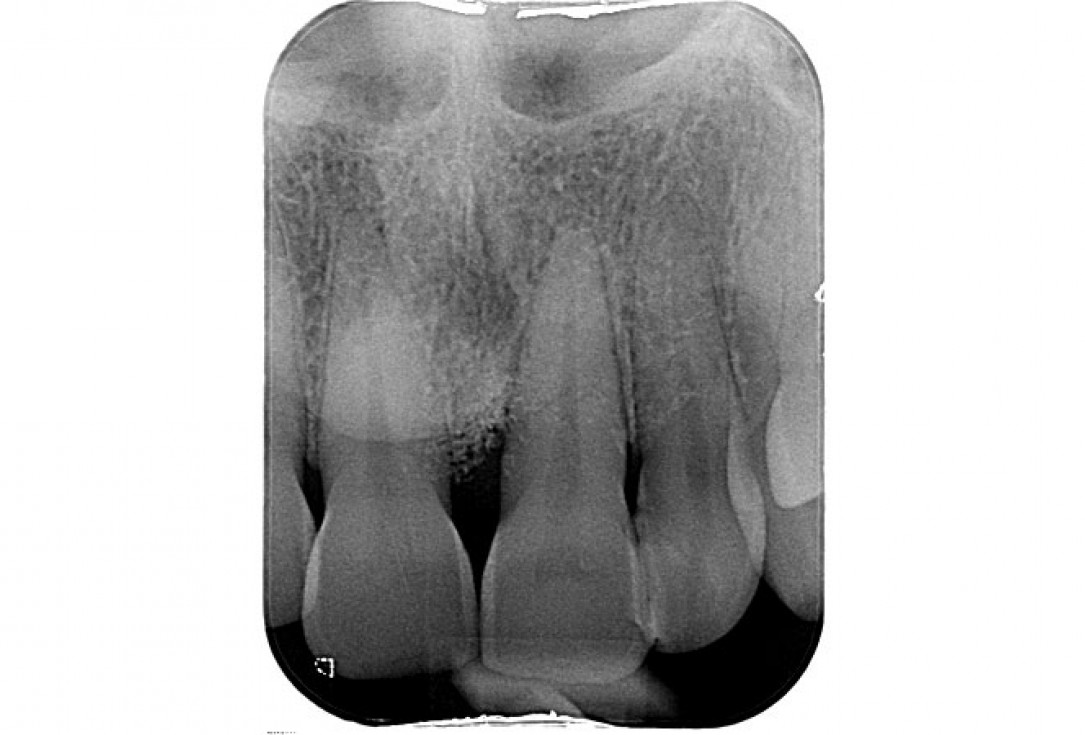

01/11 - Pre-operative radiograph.Non-contained intrabony defect treated using cerabone®, collprotect® membrane and Straumann® Emdogain® - Dr. T. Schwaar (2)